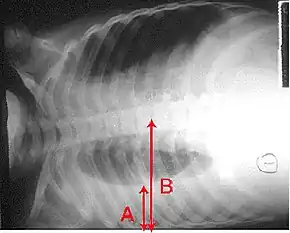

| Chest X-ray of a pneumonia caused by influenza and Haemophilus influenzae, with patchy consolidations, mainly in the right upper lobe (arrow) | |